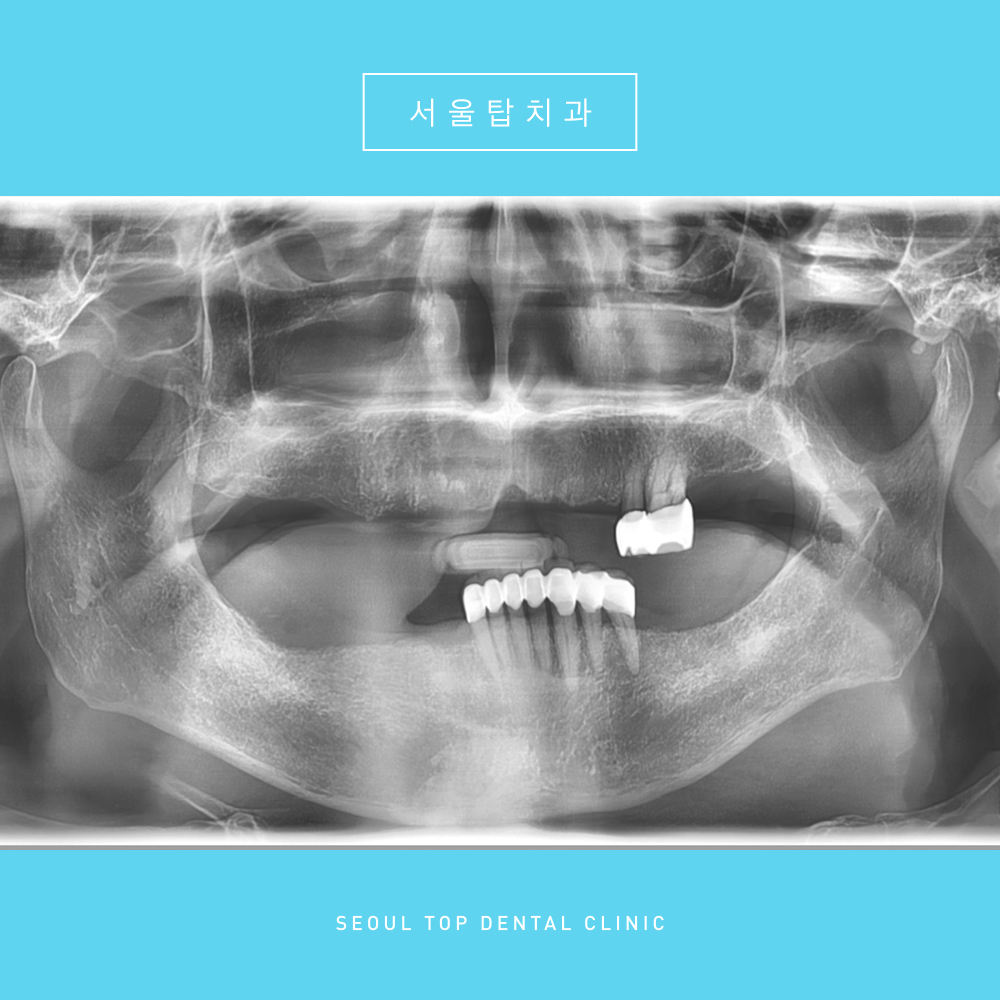

임플란트 치료를 마무리 한 후

파노라마 사진입니다.

임플란트는 치아 뿌리 역할을 하는 픽스처,

치아 머리 역할을 하는 크라운,

픽스처와 크라운을 연결하는 지대주

이렇게 3가지로 구성 되어있는데요.

파노라마 사진을 보시면

치아 머리 역할을 하는 크라운까지

모두 마무리 한 것을 확인하실 수 있습니다.